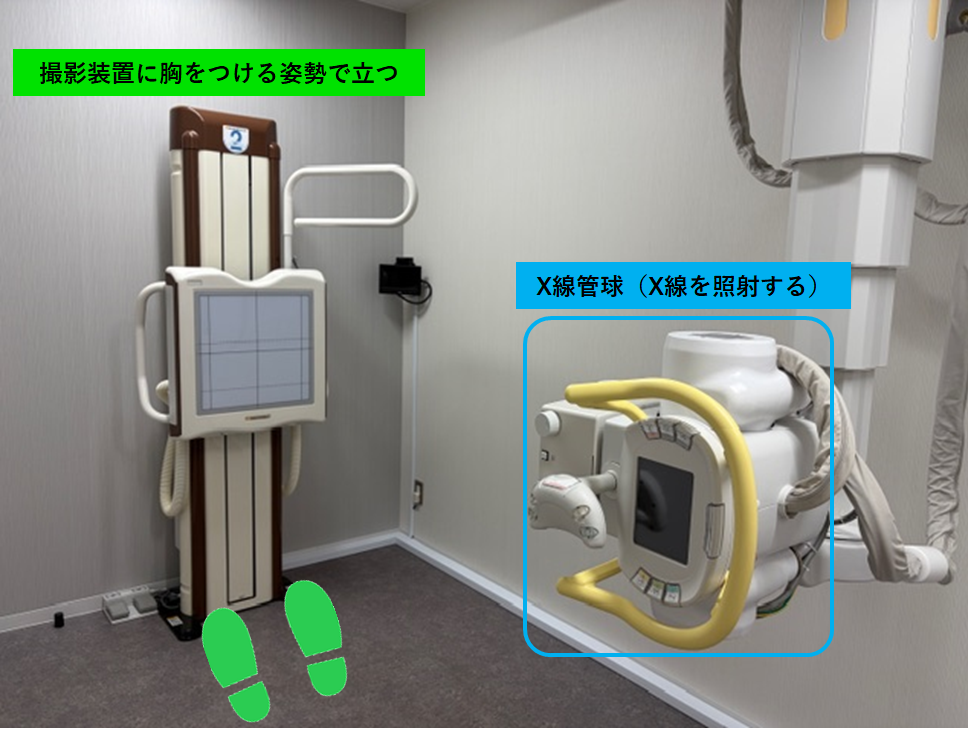

実際の撮影室の様子

胸部撮影室

撮影装置:FPD(X線を受け取り、画像を作成する)